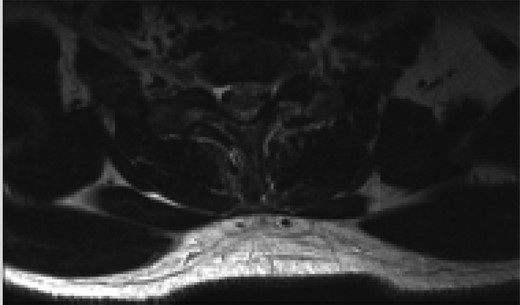

Axial T2 MRI image at C4/5 level showing central disc herniation.

Axial T2 MRI image at C6/7 level showing central annular tear with left paracentral disc extrusion behind the C7 vertebral body.